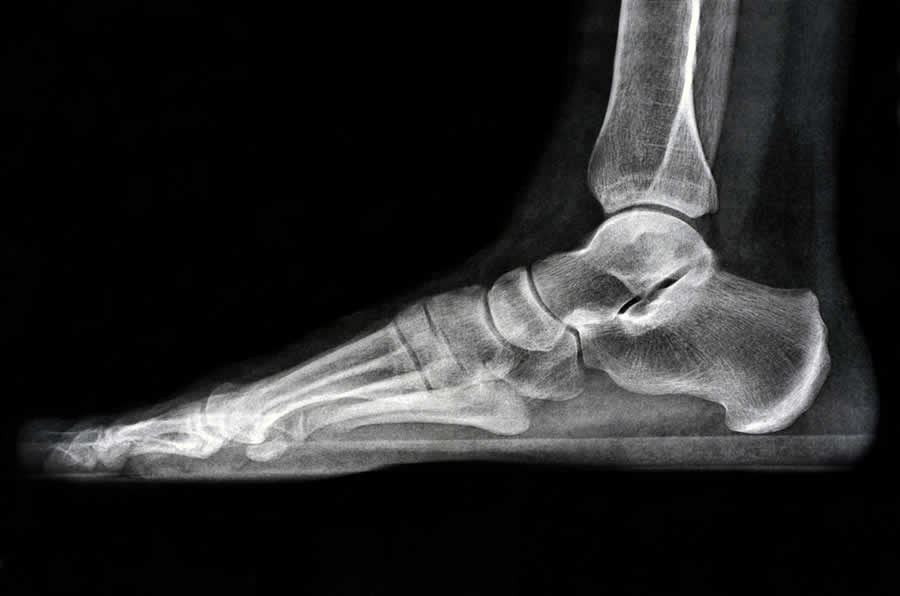

Biomechanics, in the context of podiatry, refers to the study of how the bones, muscles, and ligaments of the feet and lower limbs work together to produce movement. It’s a crucial area of focus for podiatrists because improper foot mechanics can lead to various issues, including pain, injury, and reduced mobility.

Our feet are complex structures designed to support the weight of our bodies and facilitate movement. When the biomechanics of the feet are not functioning correctly, it can lead to a chain reaction of problems throughout the body. For example, if the arches of the feet collapse (a condition known as flat feet), it can cause the ankles to roll inward (overpronation). This misalignment can affect the knees, hips, and lower back, leading to discomfort and pain.

Podiatrists analyze the biomechanics of the feet during walking (gait analysis) or standing to identify any abnormalities or inefficiencies. This analysis helps in diagnosing the root causes of foot and lower limb pain and discomfort, such as plantar fasciitis, Achilles tendonitis, or shin splints.